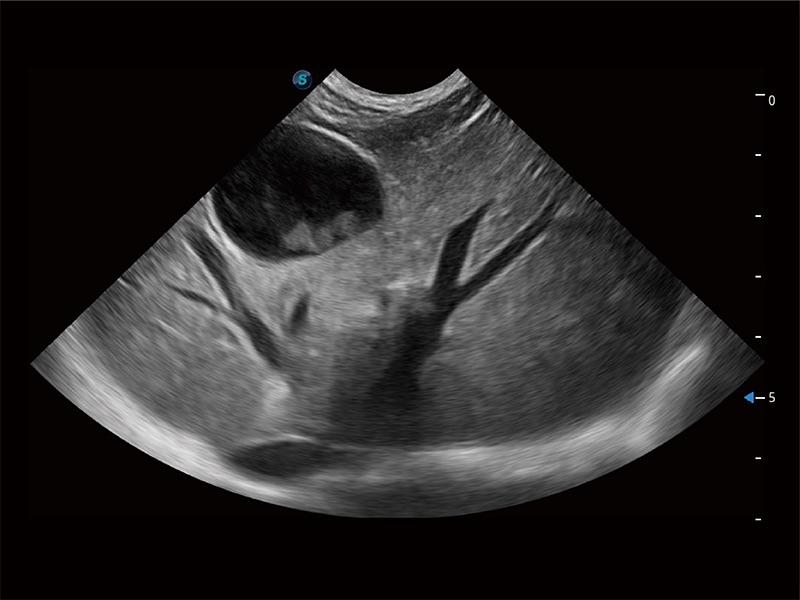

极大提升超低速微细血流的检出能力,同时更精准地滤除软组织和超声信号,为兽用医生提供以往无法通过常规血流获得的疾病诊断信息。

在传统二维血流成像的基础上,呈现血流的立体感,具有动感的生命力之美。即便是微小的血管也能轻松应对,提高了血流的视觉敏感性。

操作简便,无需高频度外力作用即可真实反映组织的形变,快速评估肿瘤良恶性。

非线性融合造影成像充分利用谐波和基波信号,为难以观察的血流进行增强显像。可用于线阵、凸阵、微凸阵、相控阵探头。